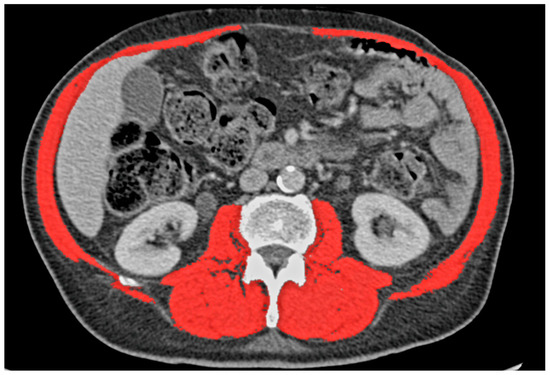

2.3. Definitions